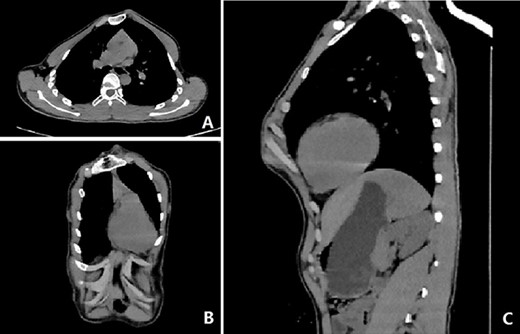

Our patient was a 15-year-old boy. He was found to have abnormal chest wall appearance at early age. The early deformity was mild but began to worsen at the age of 10 years, mainly manifested as protrusion of the anterior chest wall. He had no discomfort, but was dissatisfied with the appearance. In order to treat the deformity, he was admitted to our hospital recently for surgery. Preoperative physical examination showed that the anterior chest wall was protrusive, but there were localized depressions in the middle and below part of the chest wall (Fig. 1A, B). He also had obvious deformities of toes and fingers (Fig. 1C,D). Preoperative imaging examination revealed irregular protrusion of the anterior chest wall with localized depressions; severe distortion of sternum, costal cartilages and ribs; and mild scoliosis of spine (Figs 2 and 3). The operation was performed under general anesthesia.

Three skin incisions were made on both sides of the chest wall and in front of the xiphoid process. Wenlin procedure was completed with two steel bars to flatten the protrusion [3–5], while Wung procedure was performed with the third steel bar to support the depression [4–6](Fig. 4). During the operation, all the steel bars were fixed with Wang techniques [7]. After the bars were firmly fixed, the operation was completed and the deformity was totally corrected (Fig. 5). No complications occurred during the operation. Postoperative imaging examination showed that the positions of the steel bars were satisfactory and the thoracic shape was basically normal (Fig. 6). The patient was discharged 1 week after operation.